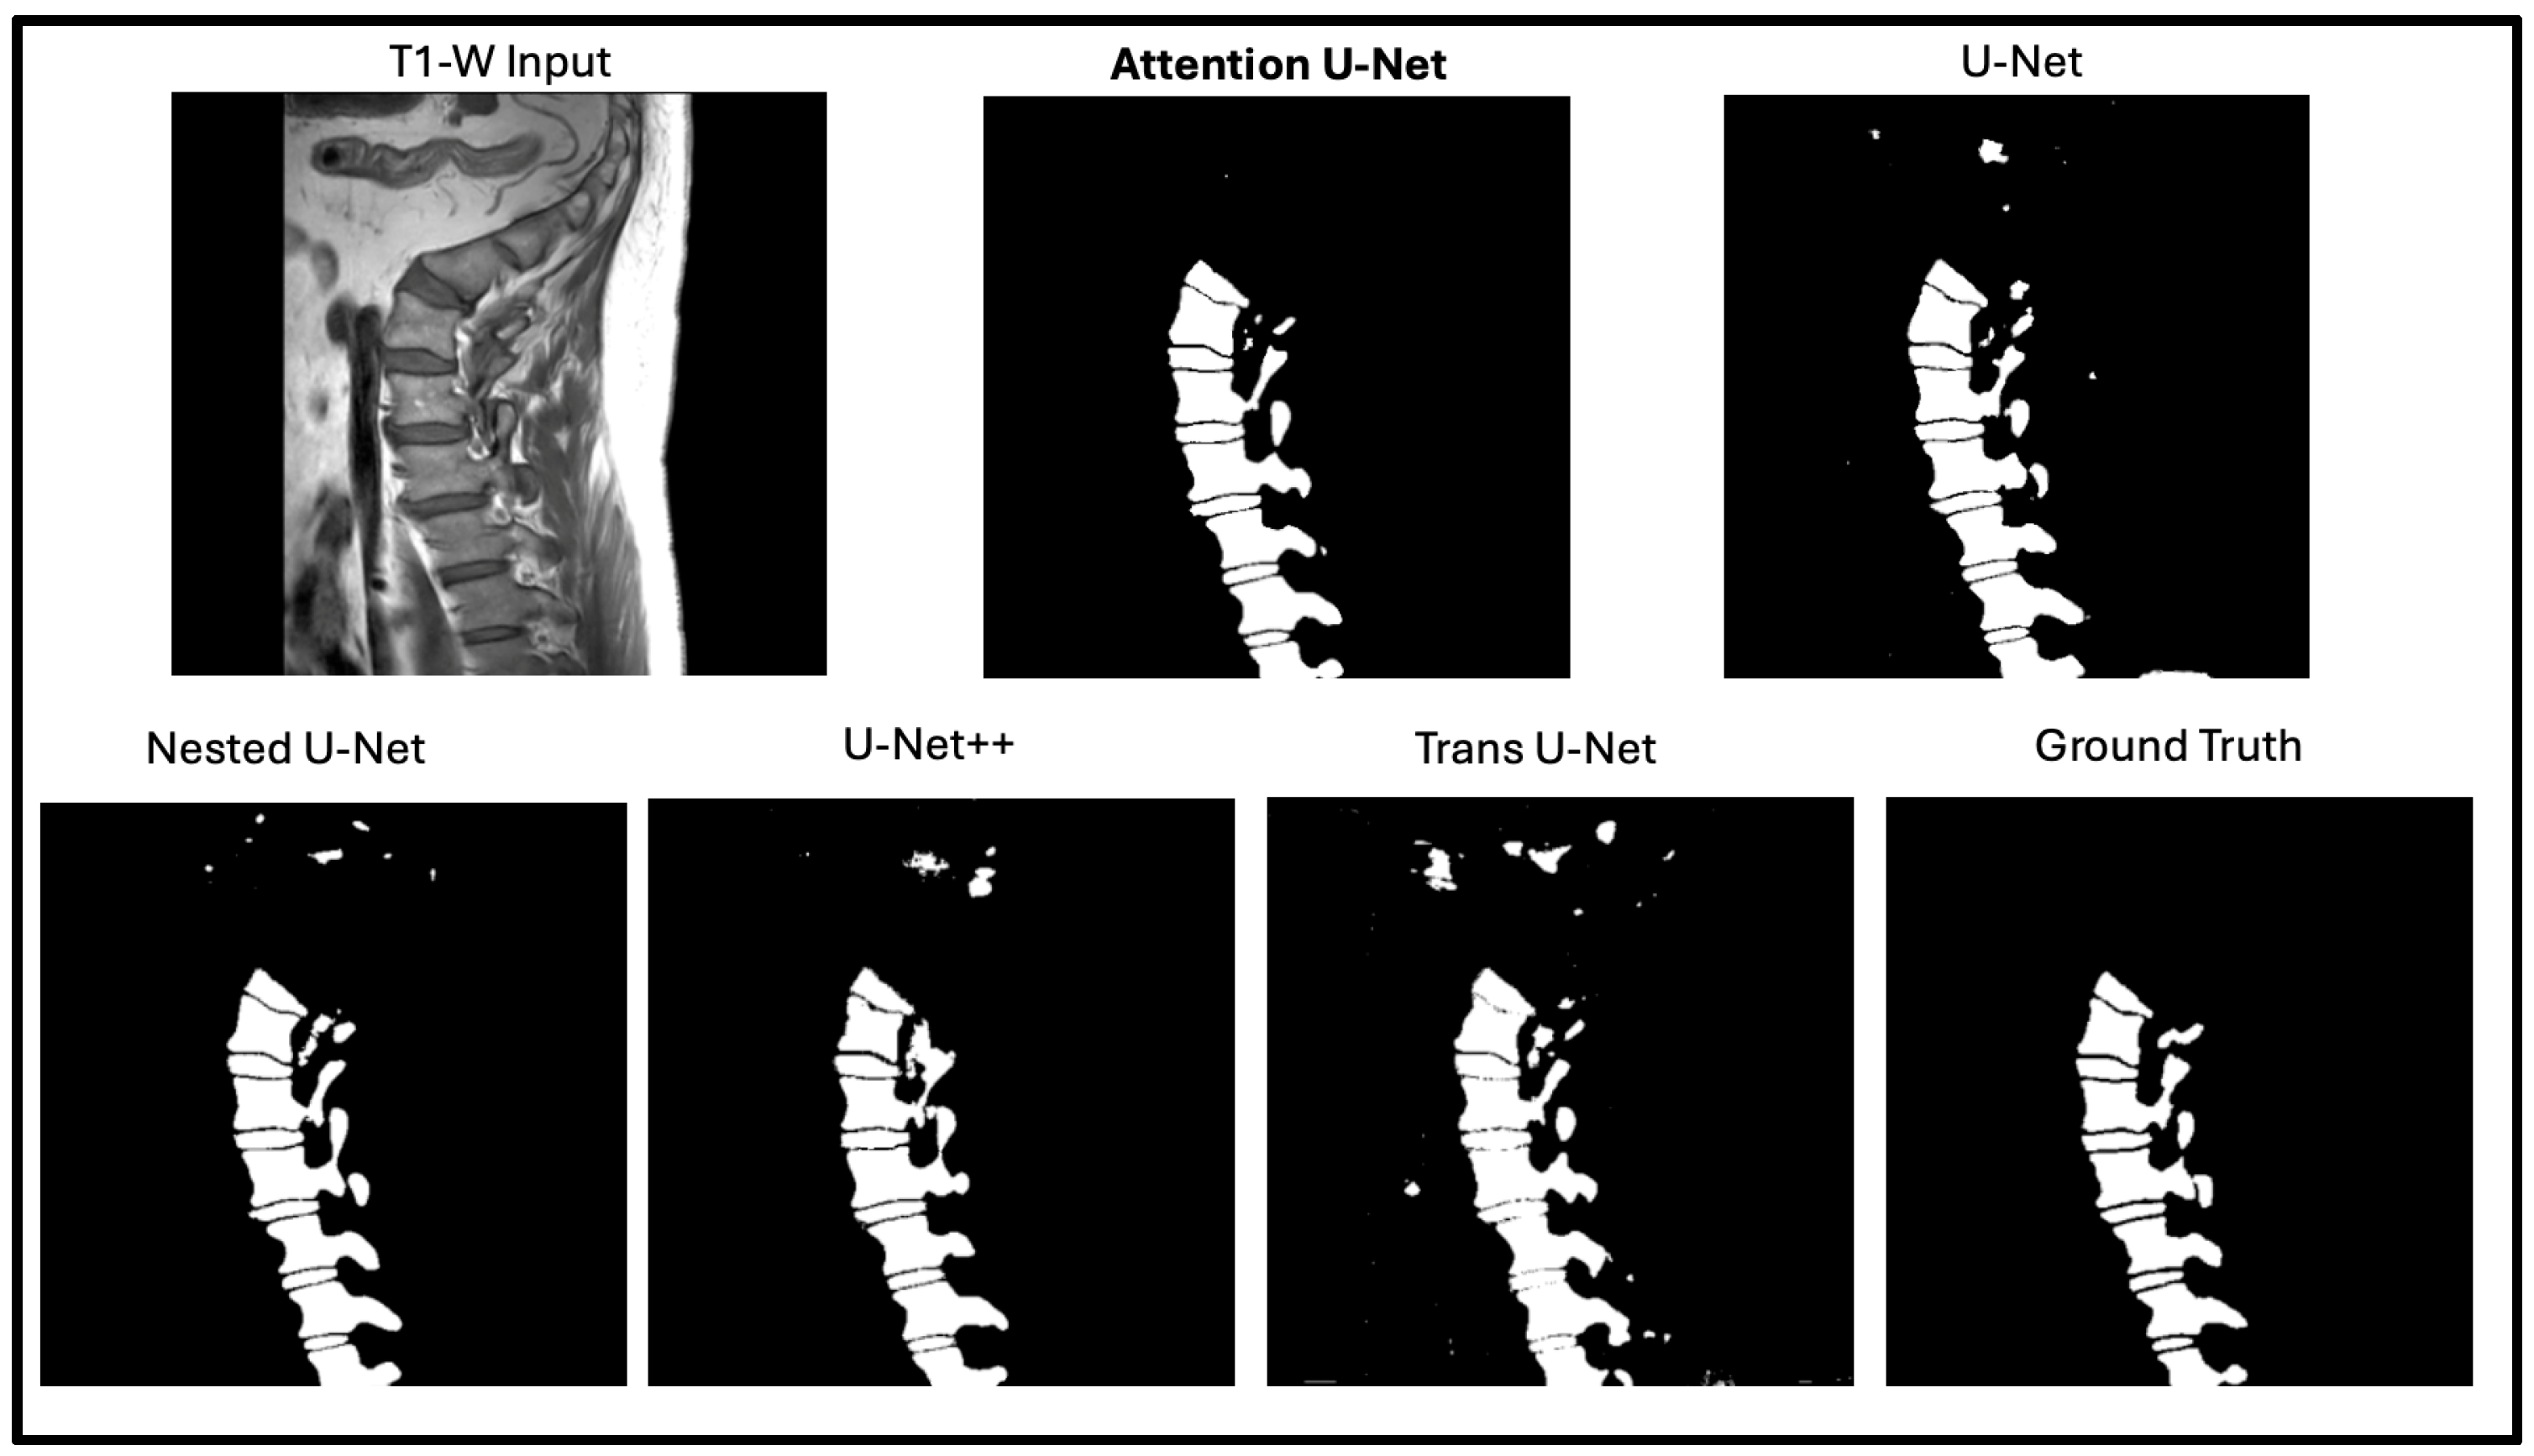

In this portion of the results, we focus on manually assessing the segmentation quality of the network outputs (Figure 5). While quantitative metrics like DICE and SSIM capture the quantitative performance of the segmentation models, we still wanted to see how these outputs are reflected in real time. DICE and SSIM might fail to highlight some subtle boundary mismatches or some issues in segmentation of complex structures. By incorporating qualitative observations, we aim to provide a more comprehensive evaluation of the network’s performance. Figure 6 shows the output of the model against the four other state-of-the-art U-Net networks. The attention U-Net is bolded as the top algorithm. Two algorithms that were close with respect to DICE, SSIM, and the radiologist reports were the Attention U-Net and the Nested U-Net. We thought it would be best if we showed the visualization to demonstrate the differences. Figure 7 highlights the difference and clearly shows the addition artifacts created by the Nested U-Net. While most of the segmentation is similar, the edges are not as clearly defined. The red boxes show the zoomed in portion of both, further demonstrating the difference between the two.

Figure 5. Qualitative comparison between Attention U-Net and Nested U-Net segmentation outputs on a lumbar T1-weighted spinal MRI. The highlighted regions show that Attention U-Net produces cleaner and more anatomically consistent boundaries, accurately following vertebral contours. In contrast, Nested U-Net introduces small artifacts and irregularities in adjacent soft tissue regions, indicating reduced boundary precision.